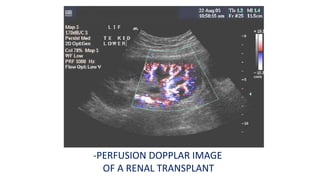

-APPLICATIONS IN INNER MEDICINES

--2-Perfusionn of Renal Transplant

-PERFUSION DOPPLAR IMAGE

OF A RENAL TRANSPLANT